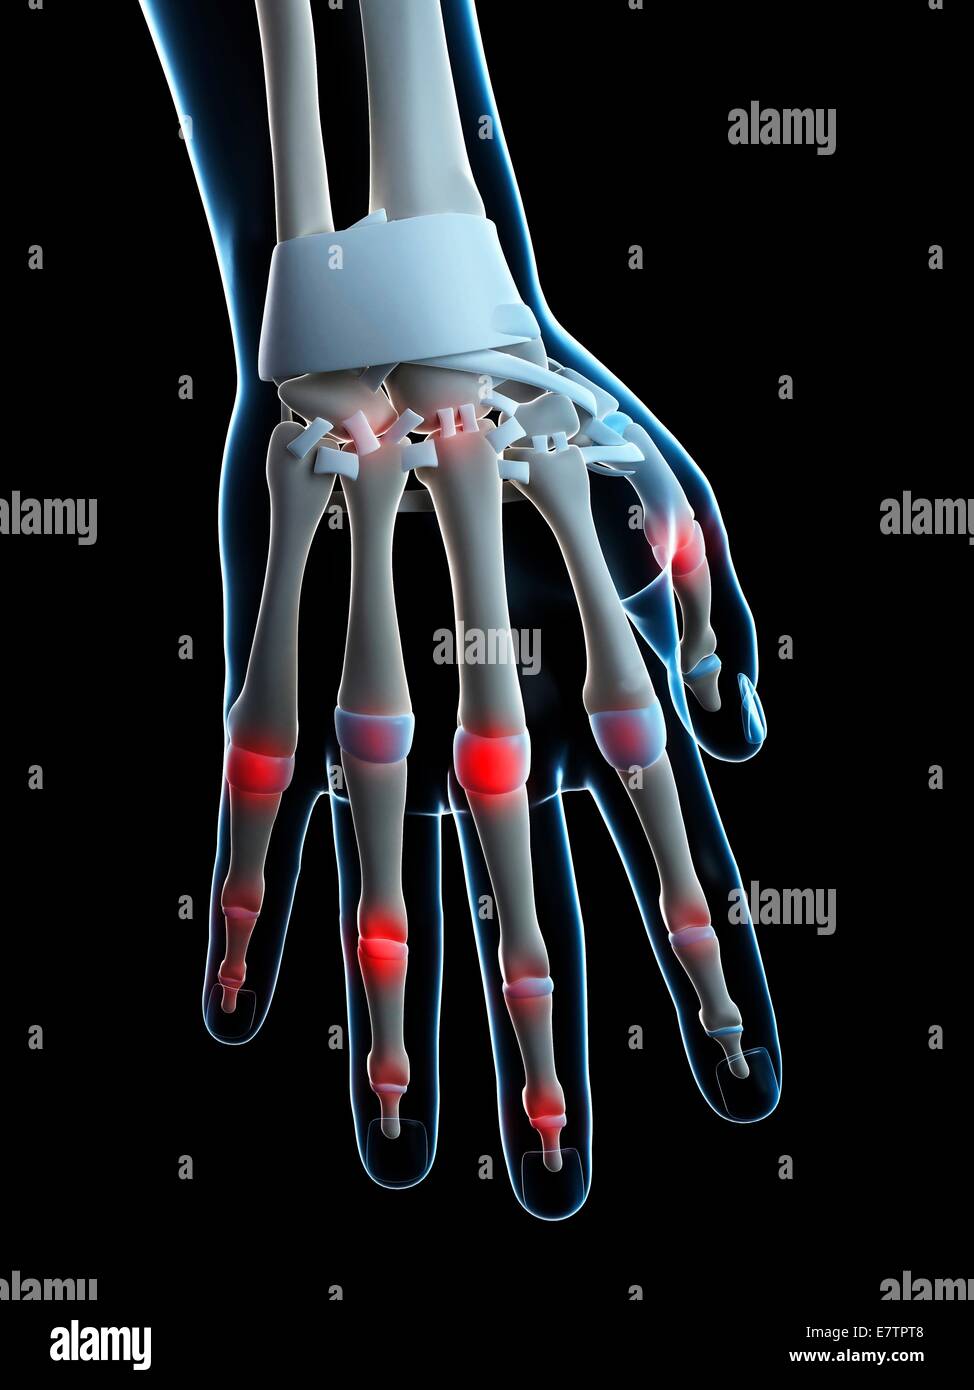

Les articulations des doigts, de l'oeuvre de l'ordinateur. Banque D'Imageshttps://www.alamyimages.fr/image-license-details/?v=1https://www.alamyimages.fr/photo-image-les-articulations-des-doigts-de-l-oeuvre-de-l-ordinateur-73688863.html

Les articulations des doigts, de l'oeuvre de l'ordinateur. Banque D'Imageshttps://www.alamyimages.fr/image-license-details/?v=1https://www.alamyimages.fr/photo-image-les-articulations-des-doigts-de-l-oeuvre-de-l-ordinateur-73688863.htmlRFE7TPW3–Les articulations des doigts, de l'oeuvre de l'ordinateur.

Les articulations des doigts, de l'oeuvre de l'ordinateur. Banque D'Imageshttps://www.alamyimages.fr/image-license-details/?v=1https://www.alamyimages.fr/photo-image-les-articulations-des-doigts-de-l-oeuvre-de-l-ordinateur-73688834.html

Les articulations des doigts, de l'oeuvre de l'ordinateur. Banque D'Imageshttps://www.alamyimages.fr/image-license-details/?v=1https://www.alamyimages.fr/photo-image-les-articulations-des-doigts-de-l-oeuvre-de-l-ordinateur-73688834.htmlRFE7TPT2–Les articulations des doigts, de l'oeuvre de l'ordinateur.

Les articulations des doigts, de l'oeuvre de l'ordinateur. Banque D'Imageshttps://www.alamyimages.fr/image-license-details/?v=1https://www.alamyimages.fr/photo-image-les-articulations-des-doigts-de-l-oeuvre-de-l-ordinateur-73688838.html

Les articulations des doigts, de l'oeuvre de l'ordinateur. Banque D'Imageshttps://www.alamyimages.fr/image-license-details/?v=1https://www.alamyimages.fr/photo-image-les-articulations-des-doigts-de-l-oeuvre-de-l-ordinateur-73688838.htmlRFE7TPT6–Les articulations des doigts, de l'oeuvre de l'ordinateur.

Les articulations des doigts, de l'oeuvre de l'ordinateur. Banque D'Imageshttps://www.alamyimages.fr/image-license-details/?v=1https://www.alamyimages.fr/photo-image-les-articulations-des-doigts-de-l-oeuvre-de-l-ordinateur-73688839.html

Les articulations des doigts, de l'oeuvre de l'ordinateur. Banque D'Imageshttps://www.alamyimages.fr/image-license-details/?v=1https://www.alamyimages.fr/photo-image-les-articulations-des-doigts-de-l-oeuvre-de-l-ordinateur-73688839.htmlRFE7TPT7–Les articulations des doigts, de l'oeuvre de l'ordinateur.

Les articulations des doigts, de l'oeuvre de l'ordinateur. Banque D'Imageshttps://www.alamyimages.fr/image-license-details/?v=1https://www.alamyimages.fr/photo-image-les-articulations-des-doigts-de-l-oeuvre-de-l-ordinateur-73688840.html

Les articulations des doigts, de l'oeuvre de l'ordinateur. Banque D'Imageshttps://www.alamyimages.fr/image-license-details/?v=1https://www.alamyimages.fr/photo-image-les-articulations-des-doigts-de-l-oeuvre-de-l-ordinateur-73688840.htmlRFE7TPT8–Les articulations des doigts, de l'oeuvre de l'ordinateur.